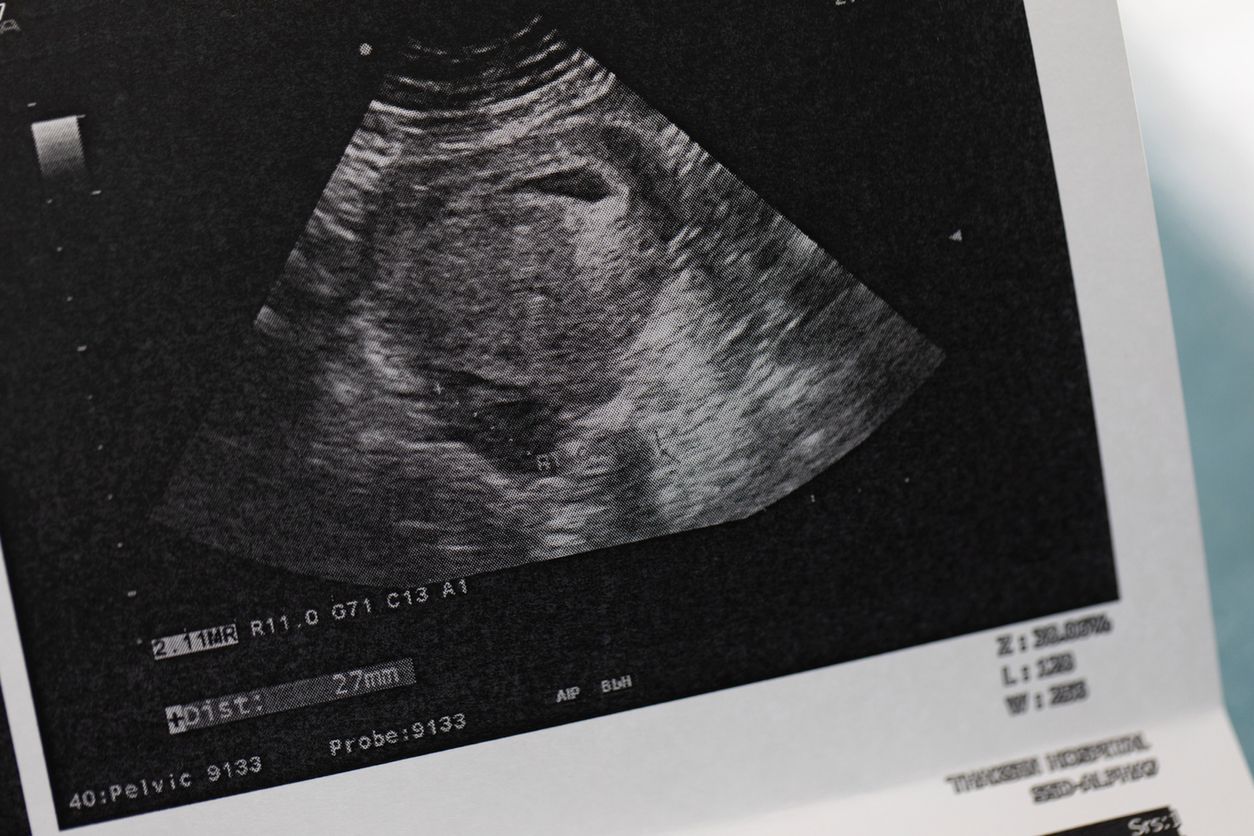

Stres pourazowy pojawia się nie tylko po wypadkach, towarzyszy też wielu kobietom po poronieniuStres pourazowy pojawia się nie tylko po wypadkach, towarzyszy też wielu kobietom po poronieniu

Źródło zdjęć: © iStock